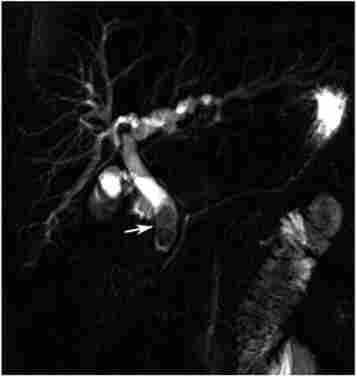

Ехографія дозволяє оцінити розміри жовчного міхура, товщину його стінки, наявність конкрементів в просвіті, а також ширину проток, розміри і щільність печінки і підшлункової залози, наявність в них вузлів і кіст, рідини в черевній порожнині. Інформативність УЗД менш достовірна для оцінки вираженості запального процесу в жовчному міхурі, ступеня деструкції його стінки, залученості в процес сусідніх органів, характеристики вмісту черевної порожнини (рис. 18.1). Звичайно, чим вища кваліфікація дослідника, тим вище роздільна здатність методу.

Ультразвукова діагностика гострого холециститу

Мал. 18.1. Ультразвукова діагностика гострого холециститу: